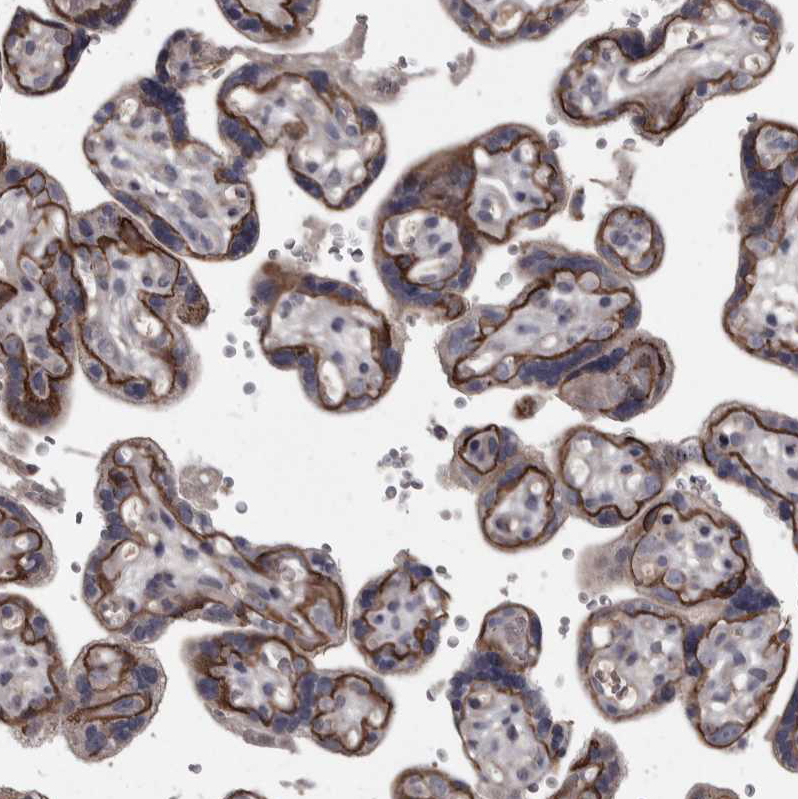

Immunohistochemical staining of human liver shows strong membranous positivity in hepatocytes.